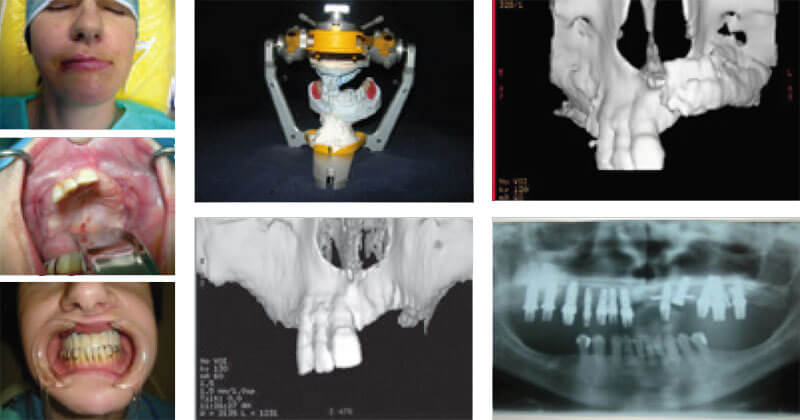

5. К Вашим услугам работает лаборатория по 3D CAD/CAM биопроектированию и моделированию.

Это позволяет решать комплекс сложных проблем, связанных с моделированием и проектированием хирургических вмешательств в челюстно-лицевой хирургии и имплантологии.

Мы изготавливаем навигационные хирургические шаблоны, биомеханические эндопротезы и т.д.

Такая конструкция изготавливается индивидуально на основании данных компьютерной томографии пациента и проектируется в 3D режиме СAD/CAM инженерных приложений. Это обеспечивает высокую точность в изготовлении конструкции. Экзоскелеты могут быть изготовлены как из медицинских сплавов титана, так и из оксида циркония.